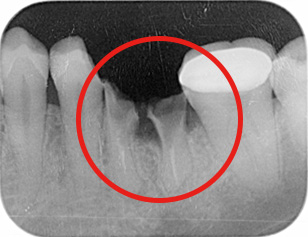

パノラマX線写真

デンタルX線写真う蝕(虫歯)も大きく、治療困難、抜歯が適応です。